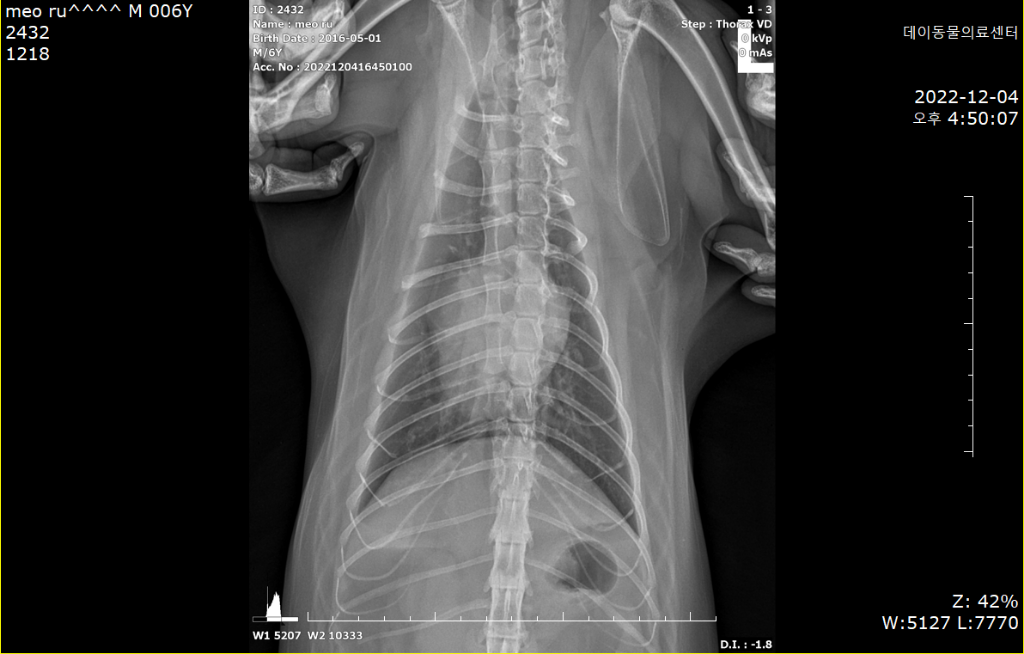

HCM이건 아니건간에 가슴쪽 엑스레이 사진에서 좌심방이 돌출하여 보이는 양상이 관찰되기 때문에

어떤 이유에서간 심장에 이상이 있을 가능성이 매우 높으니

환자의 증상에 따른 의학적 개입이 필요한 상황으로 생각됩니다.